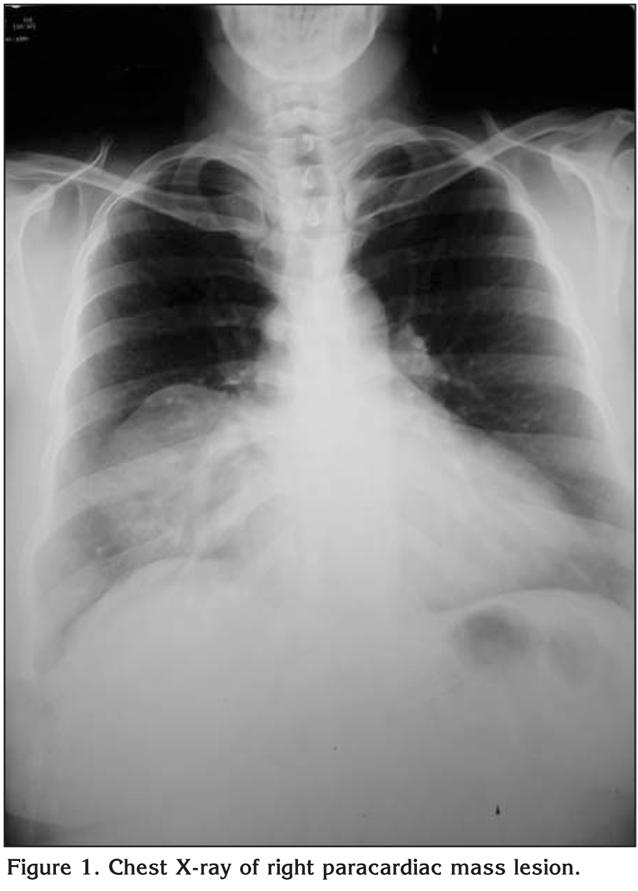

Forty three years old female patient complain from dry irritant cough, examination was free except for slight diminished air entry on the right middle lung zone. chest X-ray showed well circumscribed homogenous mass confirmed with chest CT scan to be middle mediastinal benign featuring mass (Figure 1,2). Preoperative work up were normal lab investigation and cardiac function with echocardiography.

Figure 1